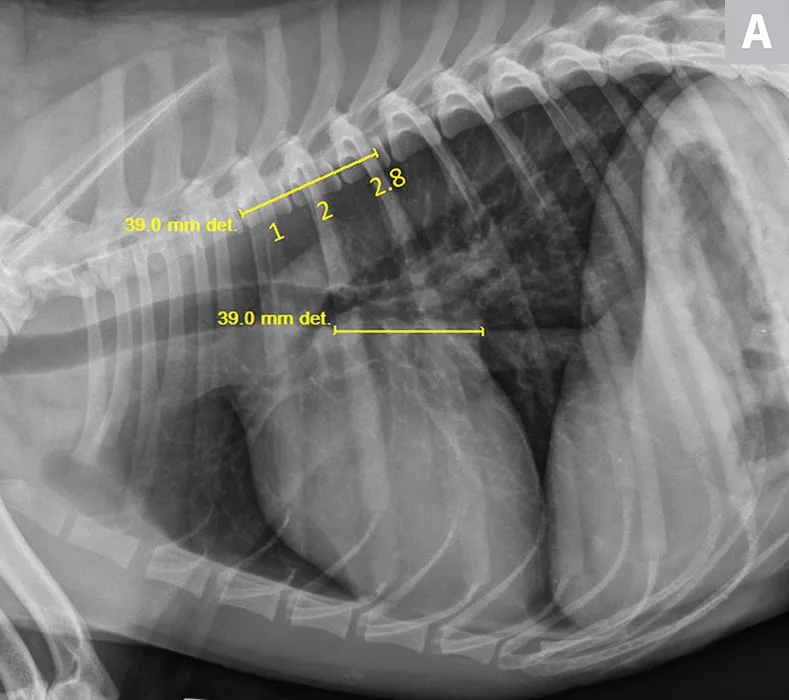

Thoracic radiographs revealed mild, left-sided cardiomegaly (Figure 2). VHS was 11 (normal, 9.2-10.3; >10.5 is suggestive of cardiomegaly in adult dogs14). VLAS was 2.8, suggesting left atrial enlargement. Based on physical examination and radiographic findings, stage B2 MMVD was suspected. Medical therapy and continued monitoring (ie, physical examinations, thoracic radiography) were recommended to identify worsening of the condition and possible progression to CHF.

FIGURE 2

VLAS measurement in a dog with suspected stage B2 MMVD using a right lateral radiograph (A). A caliper was used to measure from the center of the most ventral aspect of the carina to the most caudal aspect of the left atrium, where it intersects with the dorsal border of the caudal vena cava. This measurement was transferred to the cranial aspect of T4 and extended caudally along the thoracic vertebrae. The number of vertebrae this line transversed was rounded to the nearest tenth to determine VLAS (2.8 VBUs). Stage B2 MMVD was confirmed via echocardiography. Other structures are unremarkable. An orthogonal radiograph of the patient provides a more complete evaluation of cardiac silhouette (B); normal location of the left atrium is indicated (circle).